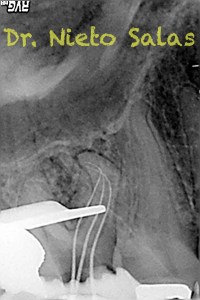

Os presento unos casos de varios molares superiores, con tres conductos mesiovestibulares con un foramen o con dos.

Una vez que tenemos medidas, obturamos los conductos: